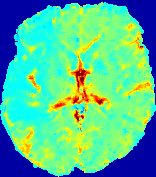

LesionRefer to captionRefer to captionRefer to captionRefer to captionRefer to captionRefer to caption𝐕rgbsubscript𝐕𝑟𝑔𝑏{\bf{V}}_{rgb}Refer to captionRefer to captionRefer to captionRefer to captionRefer to captionRefer to caption𝐕2subscriptnorm𝐕2{\|\bf{V}}\|_{2}Refer to captionRefer to captionRefer to captionRefer to captionRefer to captionRefer to captionRefer to caption3.53.53.52.82.82.82.12.12.11.41.41.40.70.70.70.00.00.0(mm/s)𝑚𝑚𝑠(mm/s)D𝐷DRefer to captionRefer to captionRefer to captionRefer to captionRefer to captionRefer to captionRefer to caption0.0200.0200.0200.0160.0160.0160.0120.0120.0120.0080.0080.0080.0040.0040.0040.0000.0000.000(mm2/s)𝑚superscript𝑚2𝑠(mm^{2}/s)Slice #1Slice #2Slice #3Slice #4Slice #5Slice #6

Figure 3: PIANO feature maps for one stroke patient, where the lesion is located in the left hemisphere. Top row: segmented stroke lesion region (white) on different slices, obtained from ISLES 2017. The corresponding slices for the PIANO feature maps are shown in the following rows.

For a better insight into an estimated velocity field 𝐕𝐕{\bf{V}} and diffusion field 𝐃𝐃{\bf{D}}, we compute the following maps: (1) 𝐕rgbsubscript𝐕𝑟𝑔𝑏{\bf{V}}_{rgb}: Color-coded orientation map of 𝐕=(Vx,Vy,Vz)T𝐕superscriptsuperscript𝑉𝑥superscript𝑉𝑦superscript𝑉𝑧𝑇{\bf{V}}=(V^{x},V^{y},V^{z})^{T}, obtained by normalizing 𝐕𝐕{\bf{V}} to unit length and mapping its 3 components to red, green, blue respectively; (2) 𝐕2subscriptnorm𝐕2\|{\bf{V}}\|_{2}: 222 norm of 𝐕𝐕{\bf{V}}; (3) D𝐷D: scalar field in Eq. 5.

Fig. 3 and Fig. 4 show the PIANO feature maps estimated from two ISLES 2017 patients: all are highly consistent with the lesion in both cases. Details of the blood flow trajectories are revealed in 𝐕rgbsubscript𝐕𝑟𝑔𝑏{\bf{V}}_{rgb} by the ridged patterns and the sharp changes of colors in the unaffected (right) hemisphere, while the flat patterns appearing within the lesion provide little directional information about the velocity and indicate low velocity magnitudes. Velocity magnitudes are more directly visualized via 𝐕2subscriptnorm𝐕2\|{\bf{V}}\|_{2}, from which one can easily locate the lesion where 𝐕2subscriptnorm𝐕2\|{\bf{V}}\|_{2} is low. D𝐷D also indicates lower diffusion values in the lesion, though with less contrast potentially due to the fact that it captures the accumulated effect of CA diffusion at the voxel-level.